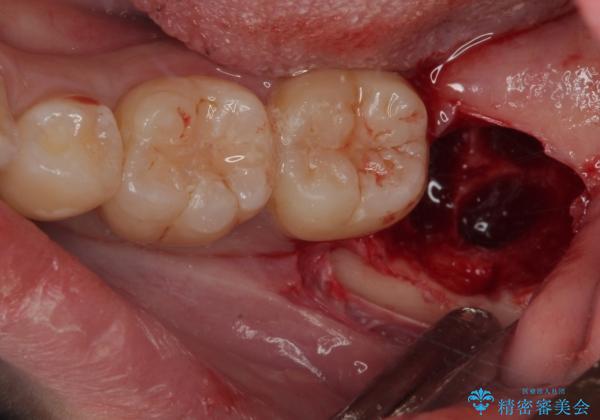

- 親知らずを抜きたいとのことで来院された患者様です。

CTで神経の位置などを確認し、抜歯術を行いました。

しっかり麻酔が効いたことを確認してから安全に抜歯を行いました。